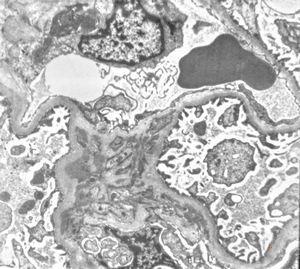

M,53y. | type III membranoproliferative glomerulonephritis